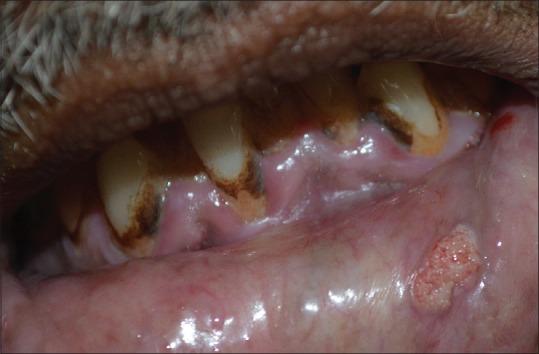

Verruciform xanthoma (VX) is an uncommon, benign, asymptomatic mucocutaneous lesion of an unknown etiopathology. It usually presents as a papule or single plaque with a verrucous or a papillomatous surface and pale yellowish to red in color. It occurs primarily on the masticatory mucosa of middle-aged individuals. We report a case of VX on the lip of a 59-year-old man. Histopathologically, VX is diagnosed by the presence of foam cells in the papillary region of the connective tissue. Differentiating a verrucous carcinoma from VX is important, especially in small superficial lesions, which may lead to inappropriate and excessive surgical intervention. Treatment of VX consists of simple surgical excision and recurrence is rare.